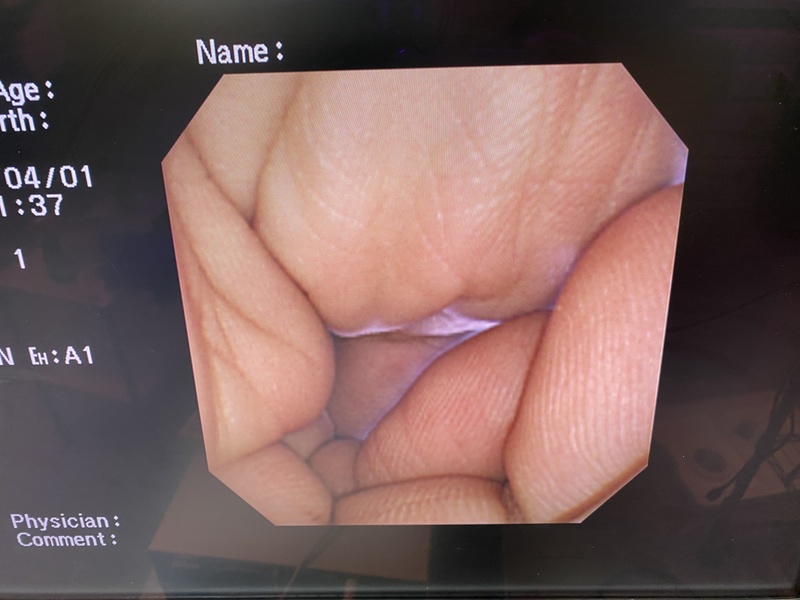

- detail Video Gastroscope / 16955 / GIF-XP260